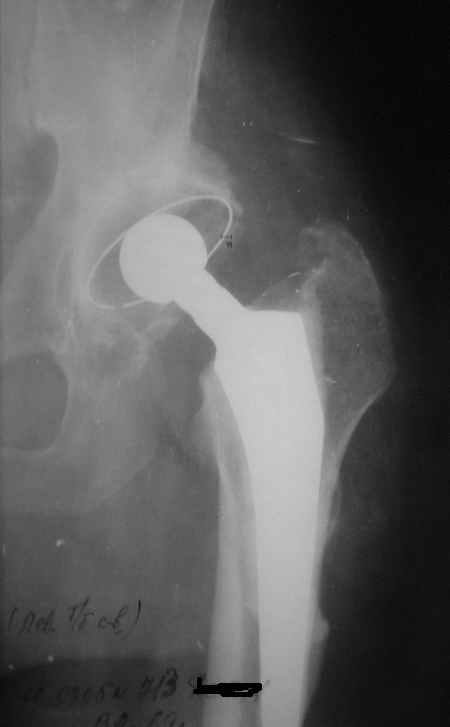

Уважаемые коллеги, Мужчина, 69 лет, в декабре 2004 г перенес тотальную цементную артропластику

Через 3 мес после операции на фоне прогрессирующих болей в средней и проксимальной третях бедра при нагрузке возникли резкие боли и появилось опухолевидное болезненно образование. Процесс сопровождался резким одномоментным укорочением ноги.

В феврале 2005 г. выполнена ревизионная артропластика, завершившаяся прогрессировавшим в течение 1-2 мес укорочением ноги. В настоящее время ходит только с костылями, при движениях в тазобедренном суставе испытывает резкие боли, ощущает хруст. Попытка осевой нагрузки бедра сопровождается ощущением "перемещения поршня" и заметным по внешним ориентирам укорочением левой ноги на 1-1,5 см.